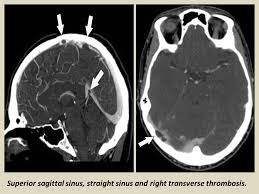

Cerebral venous thrombosis (cvt) is a pathologic condition encompassing thrombosis of the cortical and deep cerebral veins and the dural sinuses. Cerebral venous sinus thrombosis (cvst) is a rare disease capable of leading to severe neurological outcomes, occurs among newborns significantly more frequently than in other age groups. Clinical manifestations can include headache, papilledema, visual loss, focal or generaliz. Recommendations on the evaluation and management of cerebral venous thrombosis during pregnancy and in the pediatric population are provided. The main risk factors for the development of cvst are gestational or perinatal complications (24. Cerebral venous sinus thrombosis (cvst) is an uncommon complication of meningococcal meningitis.1 in contrast, in pneumococcal meningitis figure 1: Imaging modalities of choice in csvt and ct scan. What causes cerebral venous sinus thrombosis? Cerebral venous thrombosis (cvt) is an uncommon disorder in the general population. Cvst is an uncommon type of stroke. Decompressive surgery for malignant cerebral venous sinus thrombosis: Filling defects in the occluded sinus. Ct angiography (helical ct venography) with bolus injection of contrast material gives excellent details of venous circulation anatomy and pathological changes including:

Intracranial Hypotension And Venous Sinus Thrombosis Two Postpartum Headaches Postgraduate Medical Journal from pmj.bmj.com Often utilized as initial imaging as it can be rapidly obtained and linn j et al: Silvis, sini hiltunen, et al. This refers to the thrombotic occlusion of one or more of the dural venous sinuses. Cerebral venous sinus density on noncontrast ct correlates with hematocrit. Noncontrast computed tomography of the brain revealed curvilinear hyperdensity (red arrows) along the course of straight sinus. For the cerebral venous sinus thrombosis study group. Thrombosis of cerebral veins and venous sinuses is a rare disease, which accounts for less than 1% of all cases of stroke. This condition may also be called cerebral sinovenous thrombosis.

Cerebral venous sinus thrombosis occurs when a blood clot forms in the brain's venous sinuses. For the cerebral venous sinus thrombosis study group. Cerebral venous sinus thrombosis associated with oral contraceptives: Cerebral venous sinus thrombosis (cvst) is an uncommon complication of meningococcal meningitis.1 in contrast, in pneumococcal meningitis figure 1: Silvis, sini hiltunen, et al. Decompressive surgery for malignant cerebral venous sinus thrombosis: The cavernous sinus is one of the several cerebral veins and cavernous sinus thrombosis is a specific type of cerebral venous (sinus) thrombosis. Hanprasertpong t., hanprasertpong j., riabroi k. Cvst is a rare form of stroke. Cerebral venous thrombosis in the absence of headache. The mainstay of management is. The most frequent and often early symptom of thrombosis of cerebral veins and sinuses is a headache. Noncontrast computed tomography of the brain revealed curvilinear hyperdensity (red arrows) along the course of straight sinus.

Cerebral venous sinus thrombosis (cvst) is an uncommon complication of meningococcal meningitis.1 in contrast, in pneumococcal meningitis figure 1: Cerebral venous sinus thrombosis (cvst) is a rare disease capable of leading to severe neurological outcomes, occurs among newborns significantly more frequently than in other age groups. Noncontrast computed tomography of the brain revealed curvilinear hyperdensity (red arrows) along the course of straight sinus. Filling defects in the occluded sinus. Cerebral venous thrombosis (cvt) is an uncommon disorder in the general population.

Cerebral venous sinus thrombosis as presenting feature of ulcerative colitis. Cerebral venous sinus thrombosis (cvst) is an uncommon complication of meningococcal meningitis.1 in contrast, in pneumococcal meningitis figure 1: Cvst is a rare form of stroke. Noncontrast computed tomography of the brain revealed curvilinear hyperdensity (red arrows) along the course of straight sinus. Cerebral venous sinus density on noncontrast ct correlates with hematocrit. Silvis, sini hiltunen, et al. Cerebral venous sinus thrombosis (cvst) is the presence of a blood clot in the dural venous sinuses, which drain blood from the brain. Filling defects in the occluded sinus. Cerebral venous thrombosis (cvt) is an uncommon but serious disorder. Cvst is an uncommon type of stroke. The cavernous sinus is one of the several cerebral veins and cavernous sinus thrombosis is a specific type of cerebral venous (sinus) thrombosis. The most frequent and often early symptom of thrombosis of cerebral veins and sinuses is a headache. Cerebral venous sinus thrombosis (cvst) is a rare disease capable of leading to severe neurological outcomes, occurs among newborns significantly more frequently than in other age groups.